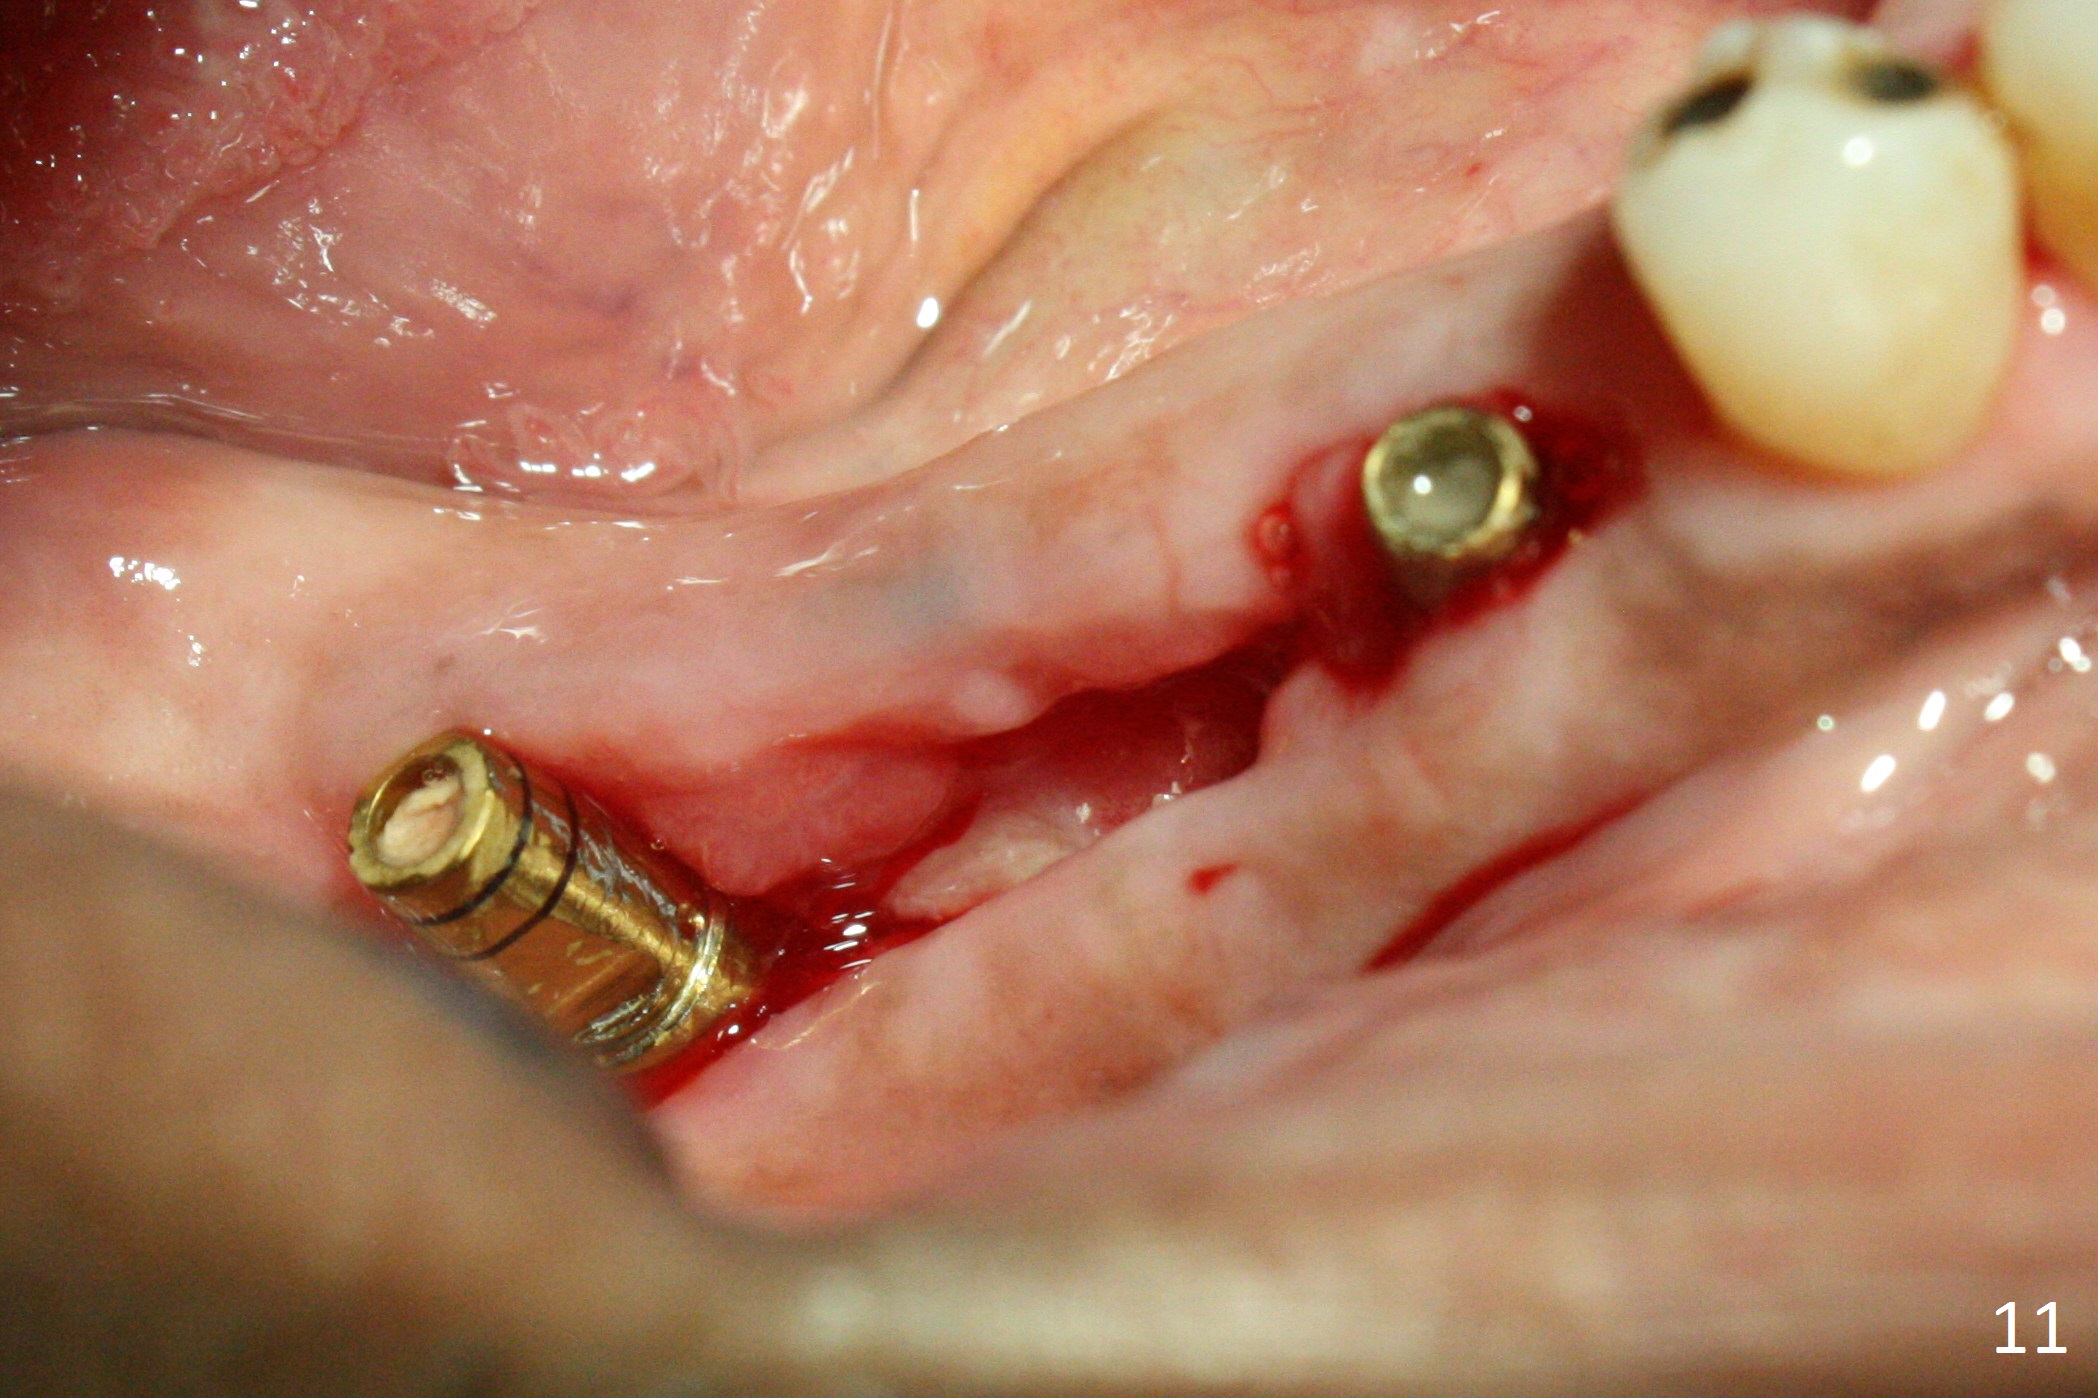

The patient is doing fine postop. He returns asymptomatic 5 weeks postop. There is minimal gingival erythema lingual to the non-resorbable membrane (Fig.10 C). After removal of plaque around the abutments, the membrane is removed (Fig.11). Two weeks later, the wound has healed (Fig.12). The abutment at #29 is basically buried, while the one at #31 is covered by the lingual gingiva.